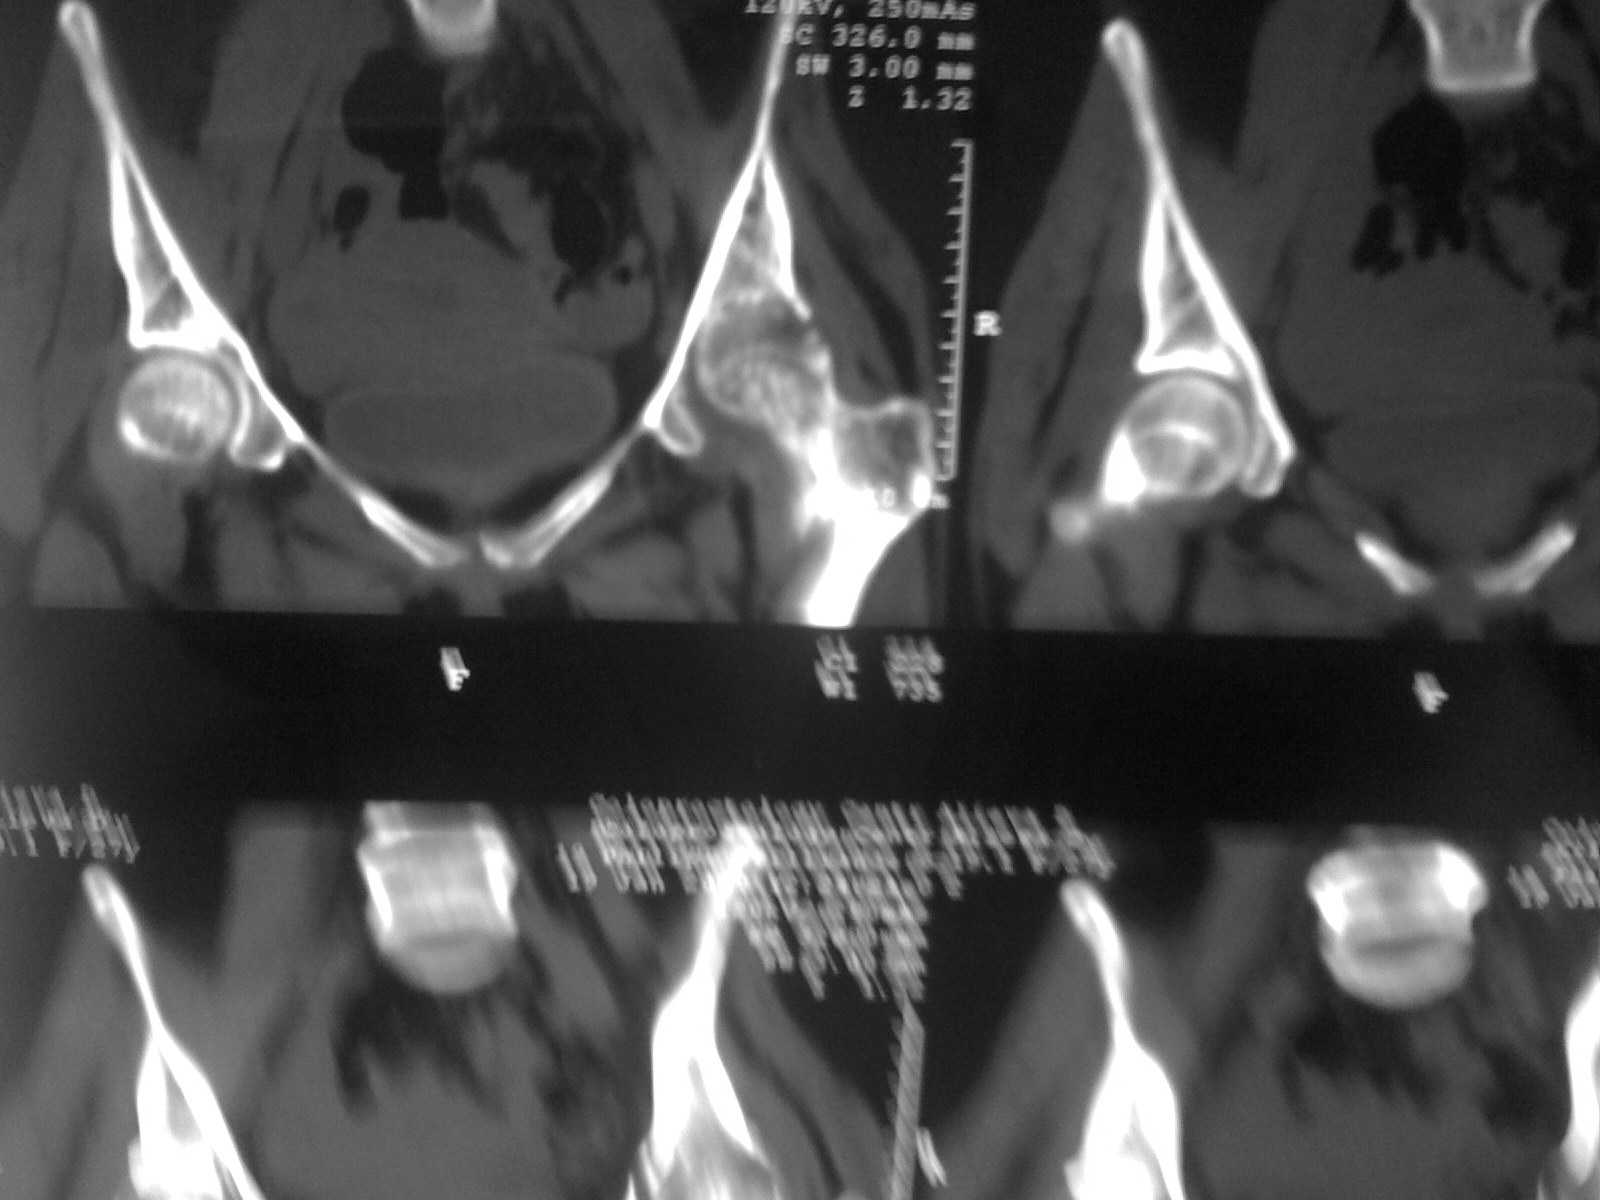

Коллеги! Пациентки 27 лет. Впервые обратилась 6 мес.назад после родов расхождение лонного

сочленения, проведена консервативно. Через 3 мес.повторное обращение по поводу болей в т\б

суставе.Ходит с костылями, отведение, приведение в суставе в пределах 10*.Укорочение

н\конечности на 3,0см.Непонятен механизм развития данной ситуации и какой метод лечения

выбрать. Если протез то какой?